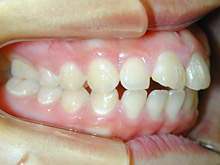

新舞子在住 I.Y様(15歳女性)

患者様は上下顎歯列弓の狭窄と上下顎前歯の叢生を主訴としてお母様とともに来院されました。

近隣のかかりつけの歯科医院で小児の頃より将来的な矯正治療の必要性をお話しいただいたそうです。

そのころからの将来矯正歯科治療の場合には抜歯の必要がある可能性も指摘されたともお話があったそうです。

犬歯関係・臼歯関係は良好です。

犬歯関係・臼歯関係は良好ですので、かみ合わせを崩さないように矯正治療をすすめます。

上下顎前歯の叢生を改善するために上下顎両側第1小臼歯を4歯抜歯して治療します。

0.14インチラウンドのニッケルチタンワイヤーで治療開始して0.16×0.16レクタンワイヤーで治療をすすめていき叢生を改善します。

できたスペースを利用して叢生の改善と臼歯のかみ合わせの改善を行います。